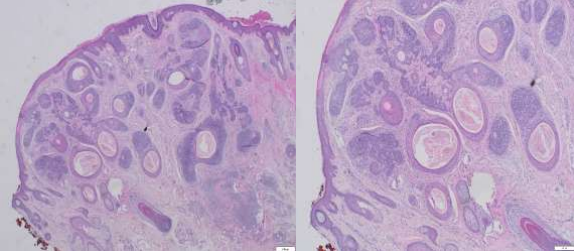

A 39-year-old male presented to the dermatology clinic of a Veterans Affairs medical center with a cystic nodule of the left medial eyebrow measuring 0.8 x 0.7 cm (figure 1). The patient was known to have CCS. His father, paternal aunt, and paternal grandfather had been diagnosed with Brooke-Spiegler syndrome (diagram 1). After presenting with multiple trichoepitheliomas, he had tested positive for a heterozygous pathogenic variant (c.2288-2289del p.Phe 763) of CYLD NM-015247.2CYLD. With this history, the clinical differential for this eyebrow lesion was cylindroma versus spiradenoma. Microscopic examination of the excision specimen revealed a well-circumscribed, dermal-based adnexal proliferation with areas recapitulating each part of the normal hair follicle: the?infundibulum, inner root sheath, outer root sheath, matrix, and bulb (figure 2.A&B). Areas resembling the infundibular portion of the hair follicle contained cystic cell aggregates lined by stratified squamous epithelium with a granular layer and filled with “basket-weave” orthokeratin (figure 2.C). Areas resembling the suprabulbar portion of the hair follicle showed clear cells as seen in the external root sheath and eosinophilic cells as seen in the internal root sheath (figure 2.D&E). Areas resembling the bulbar portion of the hair follicle showed immature basaloid cells and papillary mesenchymal bodies (figure 2.F&G). The lesion was uniformly circumscribed and without cytologic atypia, so a diagnosis of PF was rendered.

Figure 1,2,3

Figure 2